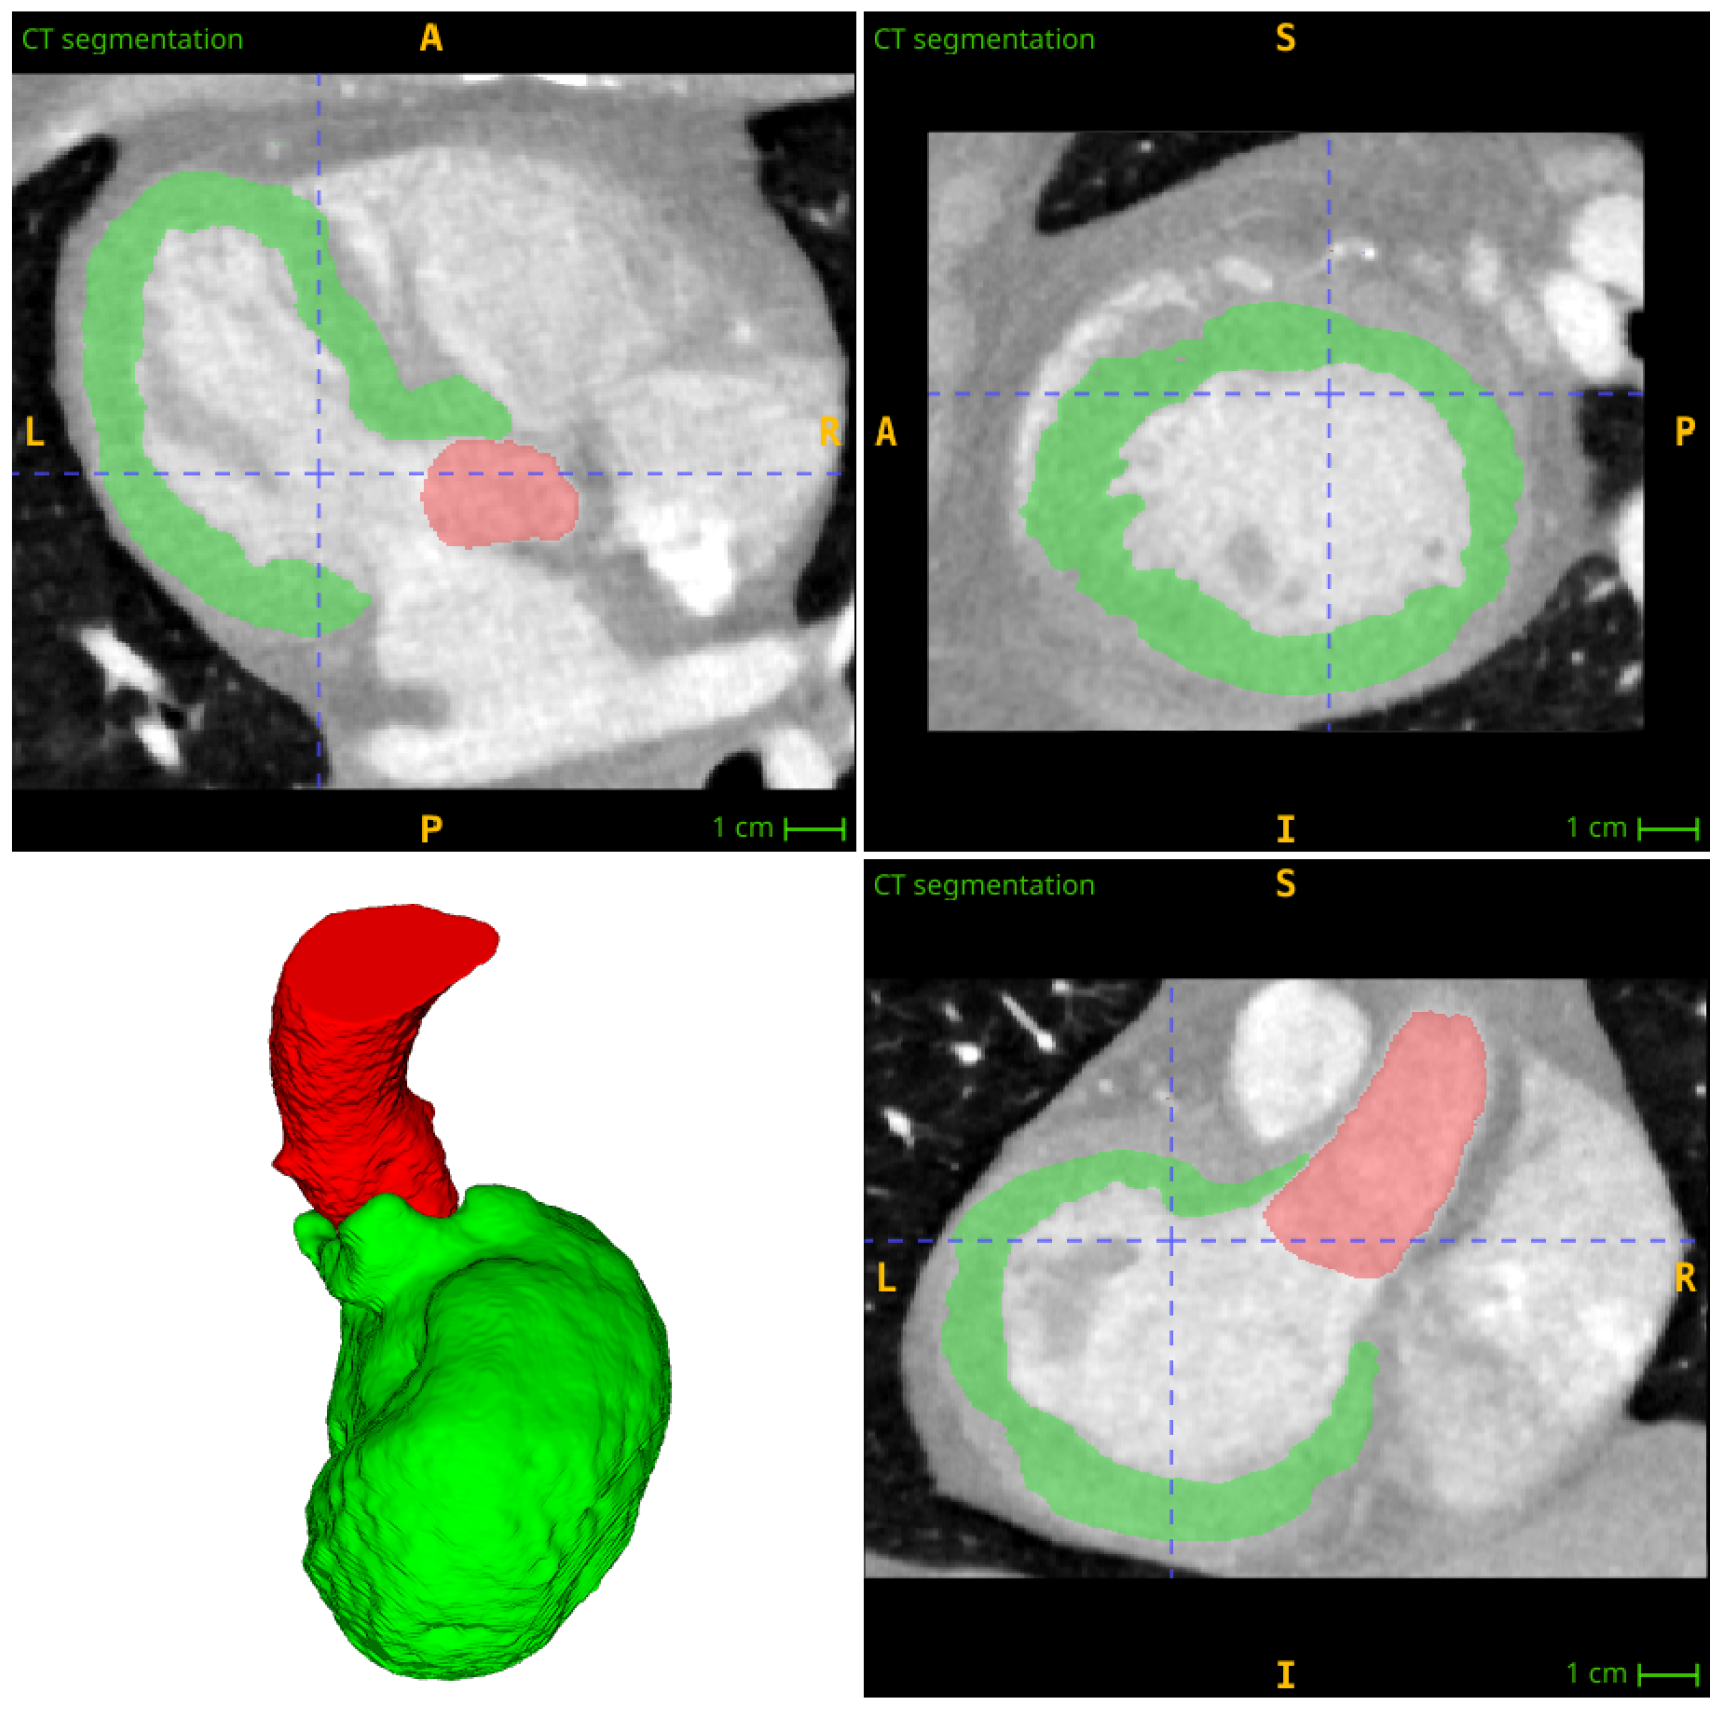

3. Segmentation and Partitioning of Coronary Vessels and Microcirculation